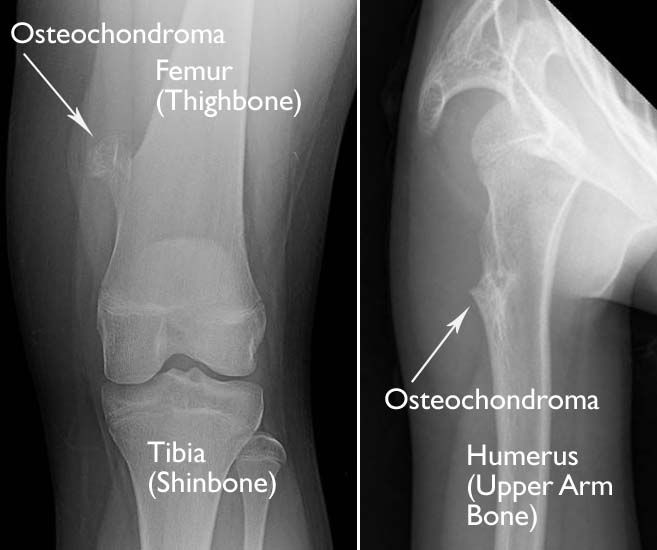

The symptoms of bone cancer include pain in the bones, the presence of a mass or lump of the bone and surrounding. It is the most severe symptom of blood cancer because of low blood platelets. Learn more about the symptoms, risk factors, diagnosis, types, treatment, and outlook for bone cancer. Bone cancer can weaken the bone it's in, but most of the time the bones do not fracture (break). Bone cancer, or osteosarcoma, usually occurs in the long bones in your legs and arms.